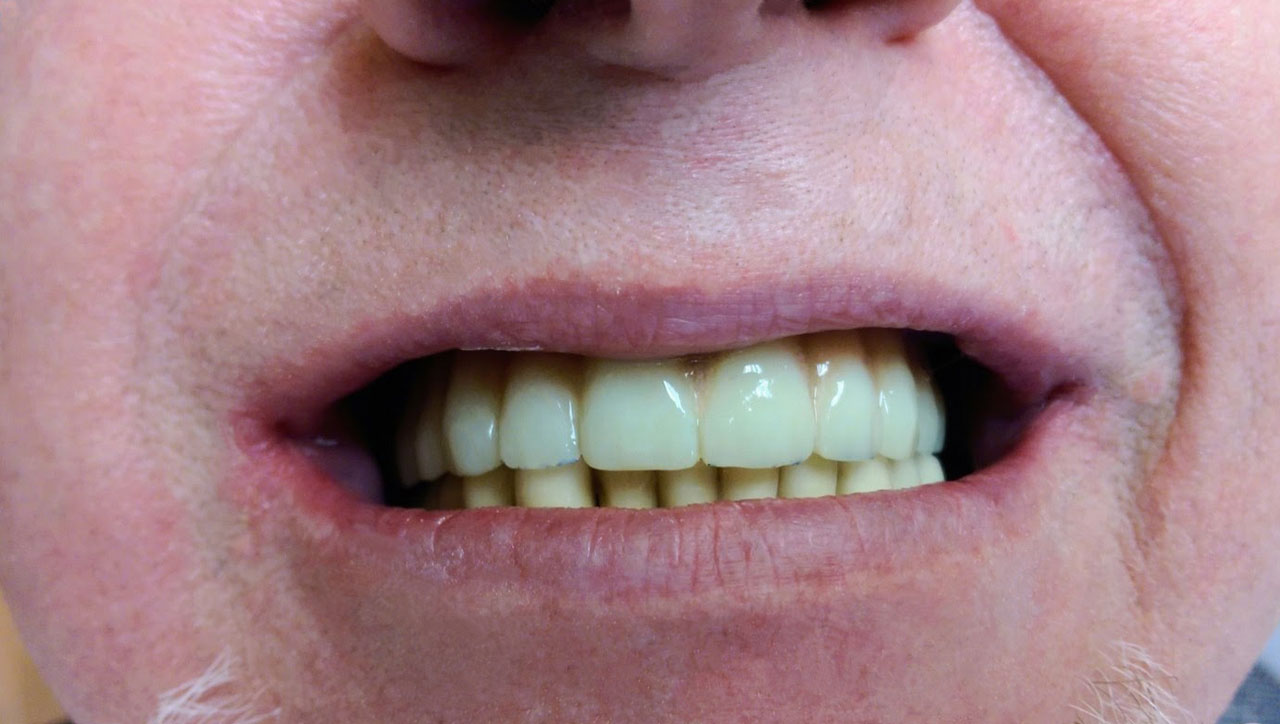

72 órával az alsó-felső állcsont teljes implantációs helyreállítása után, így mosolyog a páciens a beragasztott, fix hidakkal.

72 órávan a felső állcsont teljes implantációs helyreállítása után, így mosolyog a páciens a beragasztott, fix hiddal.